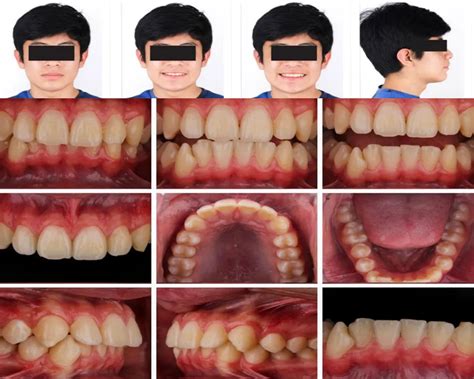

Resultados Postratamiento

Resultados Faciales

Tras el tratamiento, se ha armonizado la proporción del labio inferior con respecto al superior, siendo el aspecto facial proporcionado y simétrico (a excepción de la desviación nasal, que con el crecimiento se va haciendo más evidente). Existe una correcta exposición gingival en sonrisa, donde la presentación del material dentario se despliega en consonancia con la curvatura del labio inferior y en ausencia de zonas oscuras en los corredores bucales. En el perfil resalta un importante crecimiento nasal, con un ángulo nasolabial armónico, un tercio inferior facial proporcionado y un surco mentolabial más suave (fig. 11).

Figura 11. Fotografías extraorales postratamiento.

Resultados Dentarios

Hemos conseguido una correcta interdigitación oclusal en Clase I, habiendo solucionado la discrepancia oseodentaria inferior y el resalte, además de alcanzar un nivel de sobremordida aceptable. La paciente presenta caries a nivel de la cara oclusal de 47 y lesiones crónicas de caries (sin cavitación) a nivel de 36 y 46, por lo que remitimos el caso a su dentista para valorar estos datos. La salud gingival y periodontal es correcta (figs. 12-14).

Figura 12. Fotografías intraorales postratamiento.

Figura 13. Fotografías intraorales postratamiento. Vista oclusal.